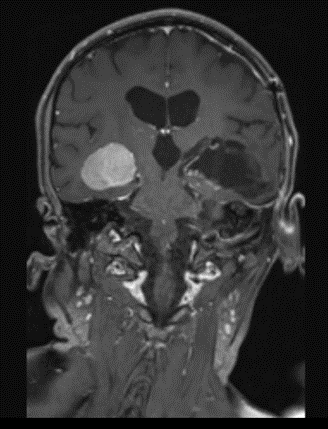

MRI outside hospital was done which was re-reported in our centre as Bilateral temporal lobe enhancing lesions. The left temporal lobe mass was larger in size and causing right-sided midline shift causing compression of the third ventricle with upstream hydrocephalus and transependymal seepage. These masses were reported as of neoplastic etiology, likely low-grade gliomas. Then MRI Brain with contrast was repeated which showed Bilateral intraventricular masses which are more or less stable in sizes causing hydrocephalus and compression effect at the level of the third ventricle towards the right side. Differentials included intraventricular tumors. No adjacent invasion is seen.

Figure 4: Lesion on T1 post contrast coronal brain MRI.

The mean age of onset with nodal disease is 20.6 years with a male to female ratio of 1.4:1 [6,17]. Patients who develop intracranial involvement, however, become symptomatic at a mean age of 34.9 years, with a strong male preponderance. In intracranial RDD, the most involved structures are the suprasellar region, cerebral convexity, parasagittal region, cavernous sinus, and petroclival region [18,19]. Radiologically, the typical MRI findings include isointense to hypointense T1-weighted signals and hyperintense T2-weighted signals with homogeneous enhancement post-contrast. Bitemporal lesions often exhibit a dural-based, meningioma-like appearance [20]. Intracranial RDD is commonly confused with meningioma and requires tumor histopathology and immunohistochemistry for its definitive diagnosis.

Bilateral temporal lobe involvement with mass effect, brainstem compression and obstruction of the ventricular system at the level of the third ventricle causing hydrocephalus is exceptional. Differential diagnosis includes several diseases (such as bilaterla glioma, PNET) in this case. A precise diagnosis could not be reached on clinical grounds alone.